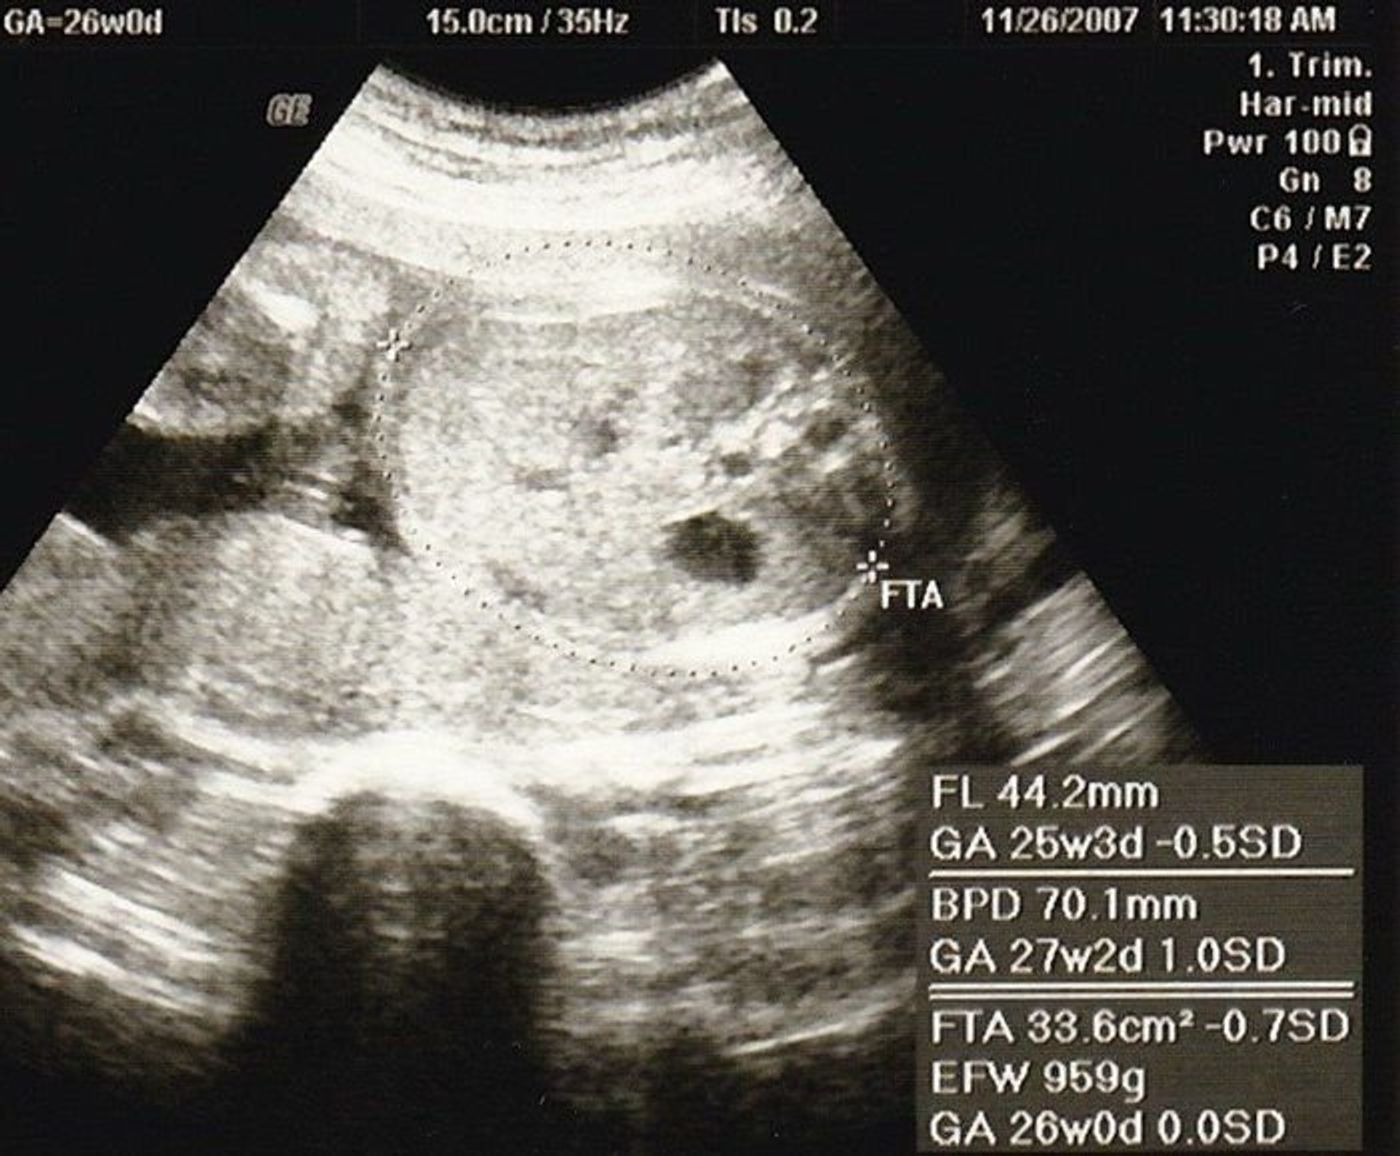

FLが平均数値よりも若干小さかったのです。が、完全に私の遺伝だと思っていました(笑)。そして26週目に標準の中に入り安心していたのを覚えています。 頭が大きい 頭の大きさを図る数値がBPD(Biparietal Diameter)とFOD(Front Occipital Diameter) があります。妊娠26週目、赤ちゃんが大きいって 2448 テーマ: 妊婦生活 26週目の妊婦健診に行ってきました。 7ヶ月に入ってから2週間おきになったので、すごく早く感じます。 今日は、前回、24週目の時にあった貧血と血糖の検査結果も聞き、 腹部エコー

妊娠中の気がかり(体重・食事・病気・体調など) Q 妊娠21週。 胎児の頭が大きく大腿骨が短いと指摘され、とても不安です。 (128) (妊娠週数・月齢)妊娠6か月 (〜23週) 21週目の妊婦健診で、胎児の頭が大きく、大腿骨が短いことを指摘されました妊娠26週目 妊娠26週目の赤ちゃんの成長 妊娠26週目の赤ちゃんの肺は活発に動き、産まれたあとの最初の肺呼吸をするための練習をしていますよ。 この時期に赤ちゃんの肺が肺サーファクタントと呼ばれる界面活性剤を作り出し始めます。 この界面活性

妊娠6カ月(週から23週)頃の大きさ 子宮の大きさは 18 センチから 23 センチが平均的。 子宮の大きさ、赤ちゃんの大きさともだんだんと個人差も大きくなってきます。 22 週になると、流産から早産にかわり、万一生まれてしまっても救命の可能性ありと 26週ごろから 胎児の頭が小さいと 言われ続けています。 エコーで見る限り異常は見られないそうですが、 ついに昨日の検診で 2週間後に糖尿の検査と、一応採血? をしてみましょうと言われました。 これは胎児に異常があるかもということでしょうか? 。 、 不安でたまりません。 。 ちなみに逆子です。 逆子の場合、頭の大きさが他の部位より正確に測れないこともあるとは聞きま 妊娠26週 胎児の体重が小さい 24週の検診時から胎児の大きさが小さめと言われています。本日26週の検診時にも同様のことを言われました。 3回食を5回食にし、甘い物を食べて下さいと言われました。